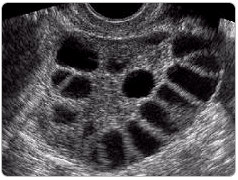

PKOS'ta Sık Görülen Bulgular